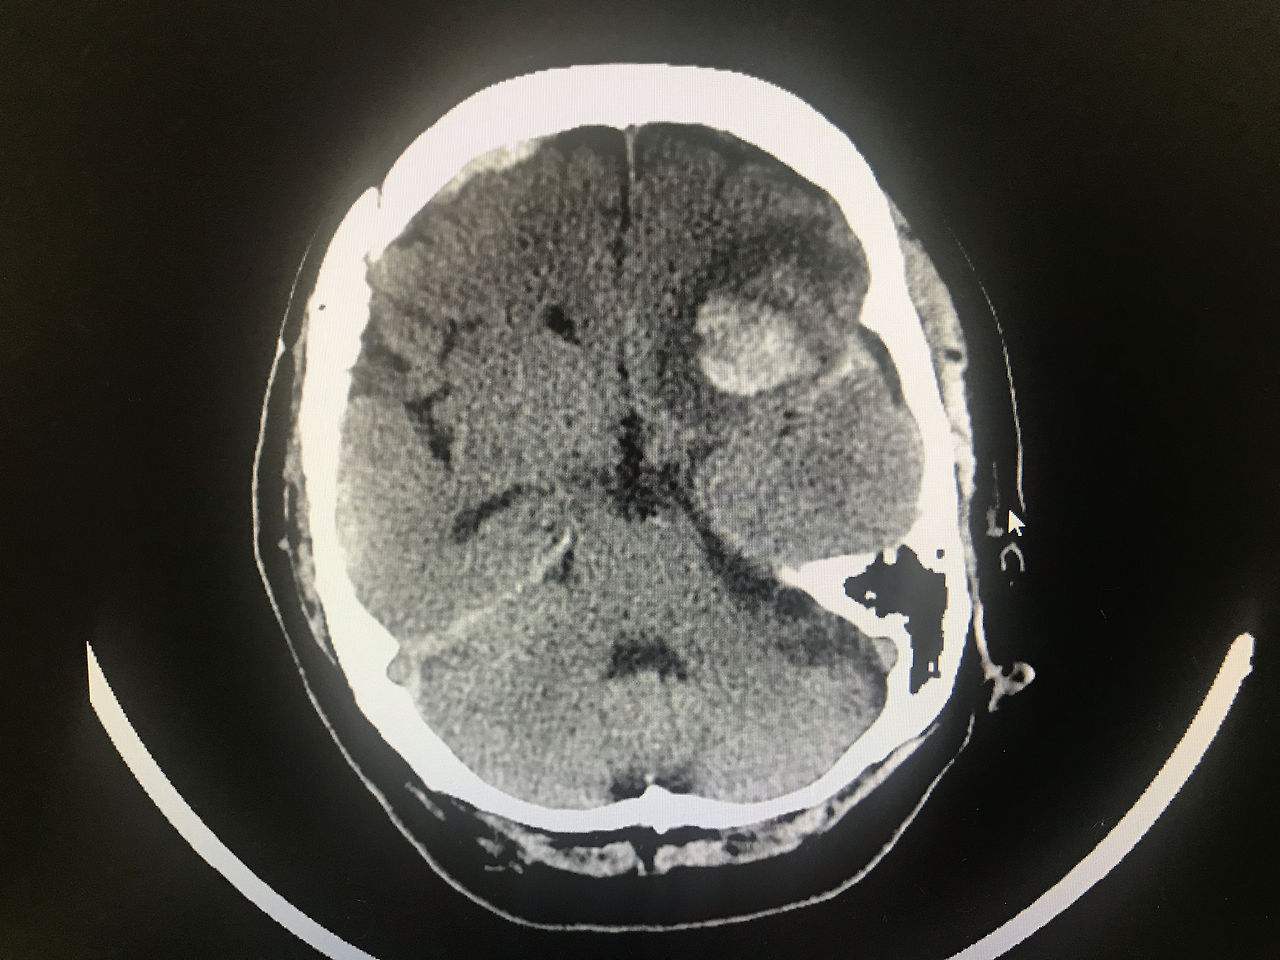

매일 소주 2~3병씩 드신다는 취객 아주머니께서 꽐라 남편(인 줄 알았는데, 나중에 보니 그냥 술친구)과 같이 119 구급대 통해 내원했습니다. 두통을 호소하시길래 brain CT 찍어보니 ICH(intracranial hemorrhage, 두개내출혈)과 SDH(subdural hemorrhage, 경막하출혈)가 같이 있네요. 잘 처치해서 중환자실로 올립니다. 이어서 심방세동으로 심계항진 호소하는 울혈성 심부전 아저씨 맞이했고요. 손이 찢어진 안하무인 취객도 줄줄이 방문하네요. 일하는 밤마다 하얗게 불태웁니다.